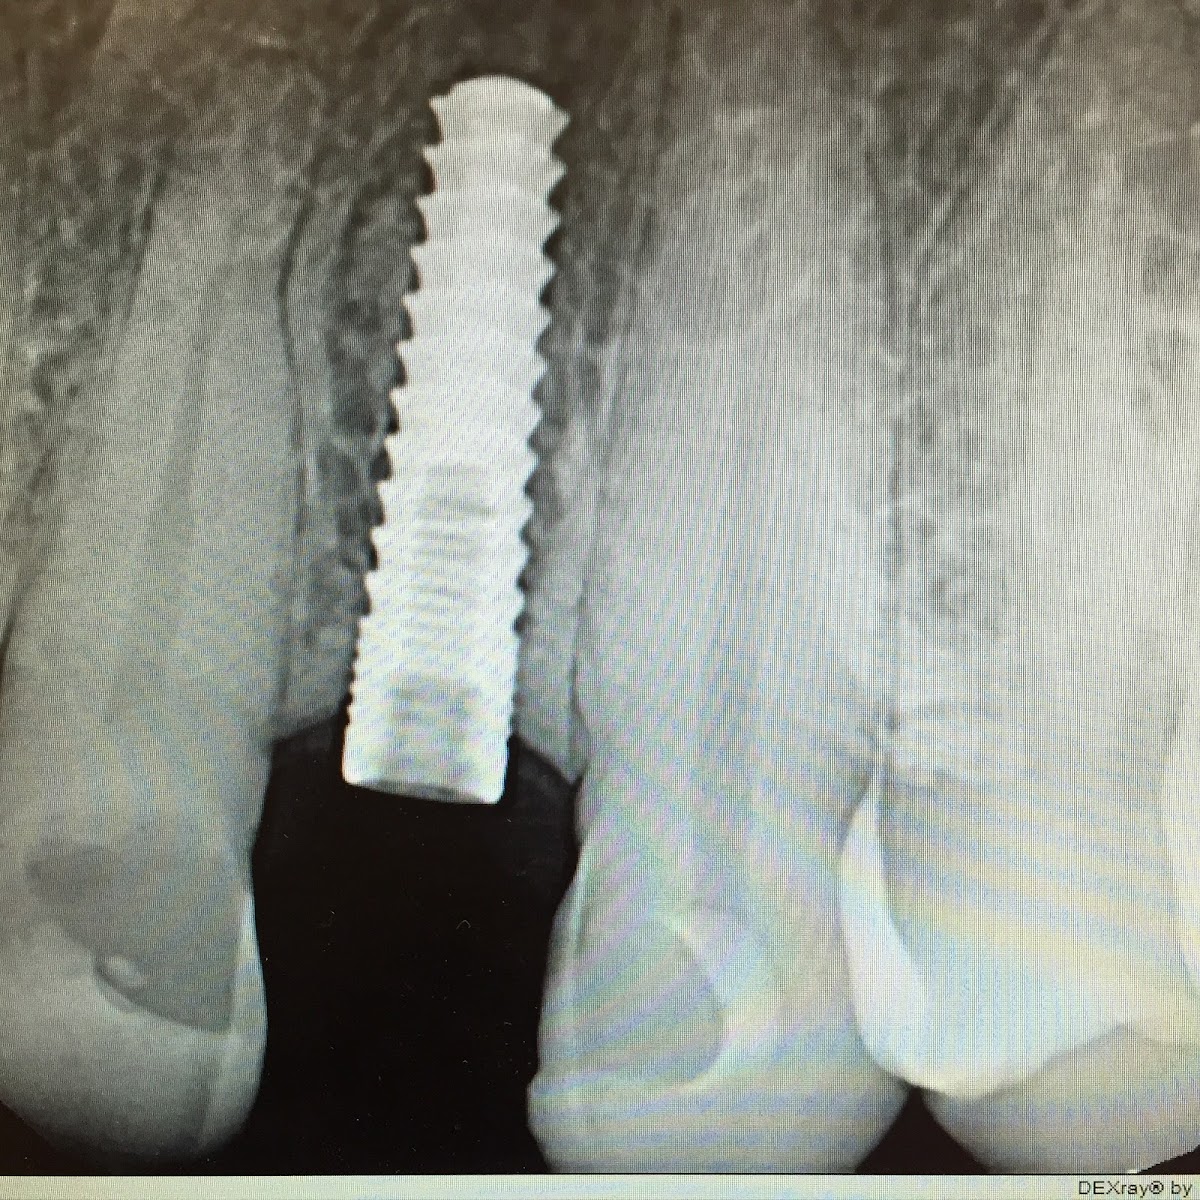

What truly sets The Smilist Dental Manhattan apart is its powerful combination of advanced technology, a multi-specialist model, and an unwavering commitment to convenience. The office is equipped with cutting-edge diagnostic and treatment tools, including digital X-rays, intraoral cameras, and advanced imaging systems. This technology allows for precise diagnoses, minimally invasive treatments, and enhanced patient understanding through visual aids. Furthermore, the practice often houses a team of dental professionals with diverse expertise—including general dentists, hygienists, and potentially specialists in periodontics, endodontics, and oral surgery—facilitating seamless, coordinated care under one roof. This eliminates the need for stressful referrals to unfamiliar offices, a significant value proposition for busy New Yorkers.

The practice's unique value proposition is deeply rooted in its 'Smilist Experience.' This encompasses transparent communication, flexible scheduling (including potential emergency appointments), a modern and comfortable office environment, and a financial team that works diligently to maximize insurance benefits and provide clear, upfront cost explanations. They understand the complexities of dental insurance and offer guidance to navigate it. The team's expertise spans the entire dental continuum, from routine prophylactic cleanings and dental examinations to more complex restorative procedures like dental implants, crowns, and bridges, as well as transformative cosmetic treatments such as teeth whitening, veneers, and Invisalign® clear aligners.